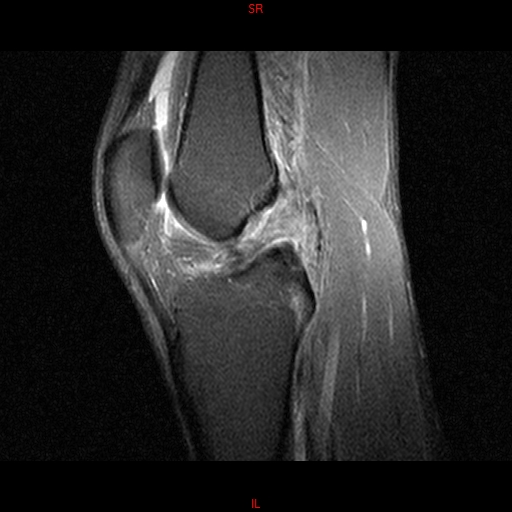

• RESONANCIA NORMAL RODILLA SAG DENSIDAD PROTONICA

• RESONANCIA NORMAL RODILLA SAG T1